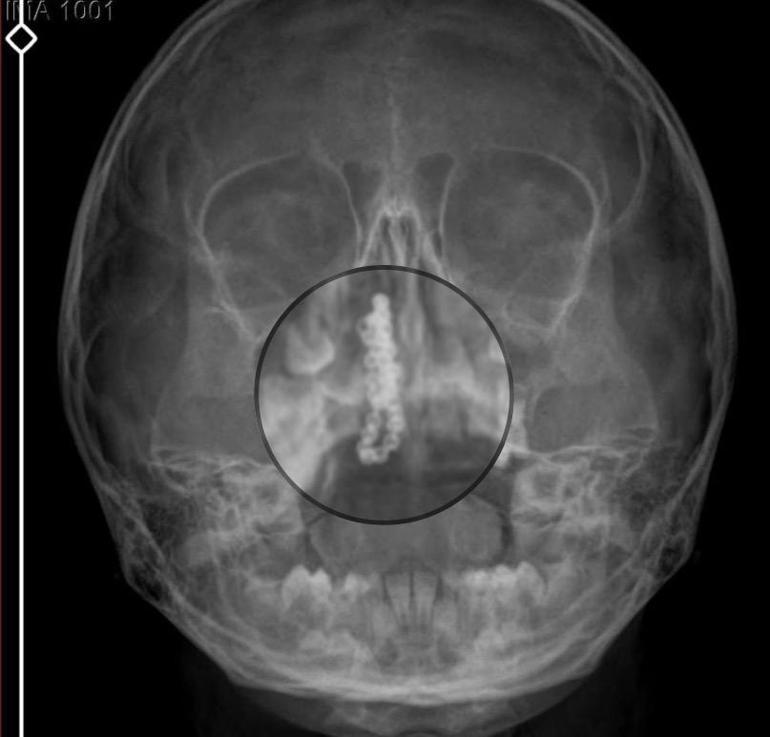

Devlet hastanesindeki doktorun ttesirksi ve içeriklı röntgen çekilmesi sonrası Polen'in burnunda metaller cisim olduğu ayrım edildi. 2 yıldır burunda kaldığı kıymetlendirilip, küçüklük top şeklinde tırnak makası zinciri olduğu belirlenen cisim, muvaffakiyetlı ameliyatla çıkarıldı.

Kızının burnundan devamlı siyah renkte akıntı olduğunu anlatan Gökhan Tekin, "Çocuğumun burnundan kanama ile devamlı siyah akıntı geliyordu. Özel hastaneye göçeşitdüm. Özel hastanede filmler çekildi, hiçbir bulguya rastlanılmadığı söylendi. O siyah leke da enfeksiyona dayalı olan tek şeyler olduğu bize söylendi. Eve geldik, akıntı sürmesi üzerine bu kez devletleri hastanesine başvurduk. Burunda metaller zinciri ayrım ettiler. Böyle tek ihmalkarlık olabilir mi? Özel hastaneye gidiyoruz, paramızla rezil oluyoruz. Zincir, 2 yıldır burnunda ve devletimizin hastanesinde iyice tek doktorumuz zinciri ortaya çıkarıyor, kızım ölümden dönüyor. Ben sonuna kadar bu işin peşini bırakmayacağım. Sonuna kadar hukuk mücadelesi vereceğim. Bu da diğer hastalarımıza ibret olsun. İşte, bakın eşleri tek zincir. 'Bulguya rastlanılmadı' deniliyor" dedi.